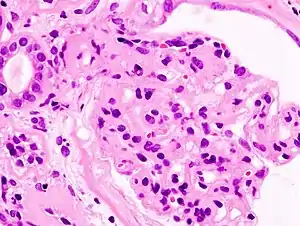

Sindromul nefrotic este un complex de manifestări clinice, urinare și bioumorale secundare unei proteinurii ce depășește 3,5g/1,73 m2 suprafața corporală pe zi. Proteinuria se asociază frecvent cu hipoalbuminemie (sub 3g%), hiperlipemie, hipercolesterolemie, lipidurie și edeme. Deși are o etologie variată, tulburarea fiziopatologică fundamentală este hiperpermeabilitatea membranei bazale glomerulare, ceea ce determină proteinuria.